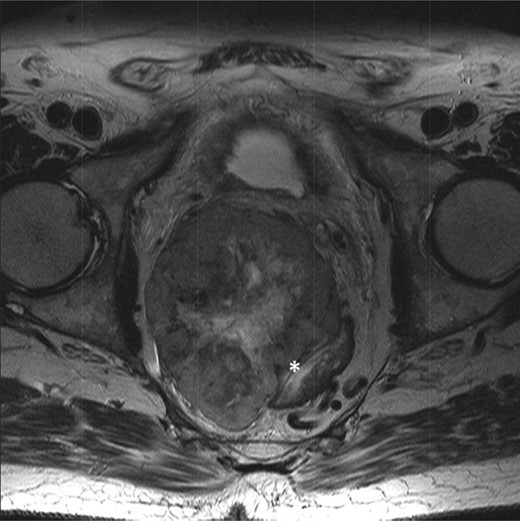

The multidisciplinary team review advised neoadjuvant treatment with imatinib mesylate and further reassessment. Repeat MR pelvis and staging PET CT abdomen, thorax and pelvis were then performed. These showed a large extra-luminal tumour with downsizing in tumour bulk (6 × 5.7 × 5.4 cm) (Figs 3–5) but in close approximation with the right seminal vesicle.

T2-weighted axial images after 3 months of imatinib mesylate therapy. The mass has shown a significant reduction in size (white star).